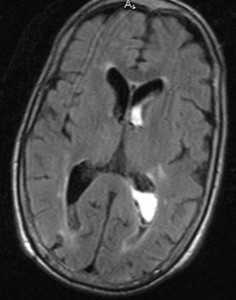

Субдуральная гематома обычно возникает вследствие разрыва вен. Причины субдуральной гематомы - травма, антикоагулянтная терапия, резкая декомпрессия при шунтировании желудочков по поводу гидроцефалии. Очень редко встречаются субдуральные гематомы при разрыве аневризм и АВМ. Клинические проявления связаны смасс-эффектом. Частота субдуральных гематом составляет около 1 случая на 10 тысяч населения. Располагаются субдуральные гематомы по конвекситальной поверхности, изредка, вдоль межполушарной щели и намёта, в области задней черепной ямки. Может быть сочетание субдуральной гематомы с кровоизлиянием в соседние участки мозга. прогноз в этих случаях неблагоприятный. Отображение гематомы на КТ и МРТ зависит от их давности. Субдуральные гематомы имеют форму серпа.

![Субдуральная гематома подострая]()

МРТ головного мозга. Аксиальная Т2-взвешенная МРТ. Подострая субдуральная гематома.